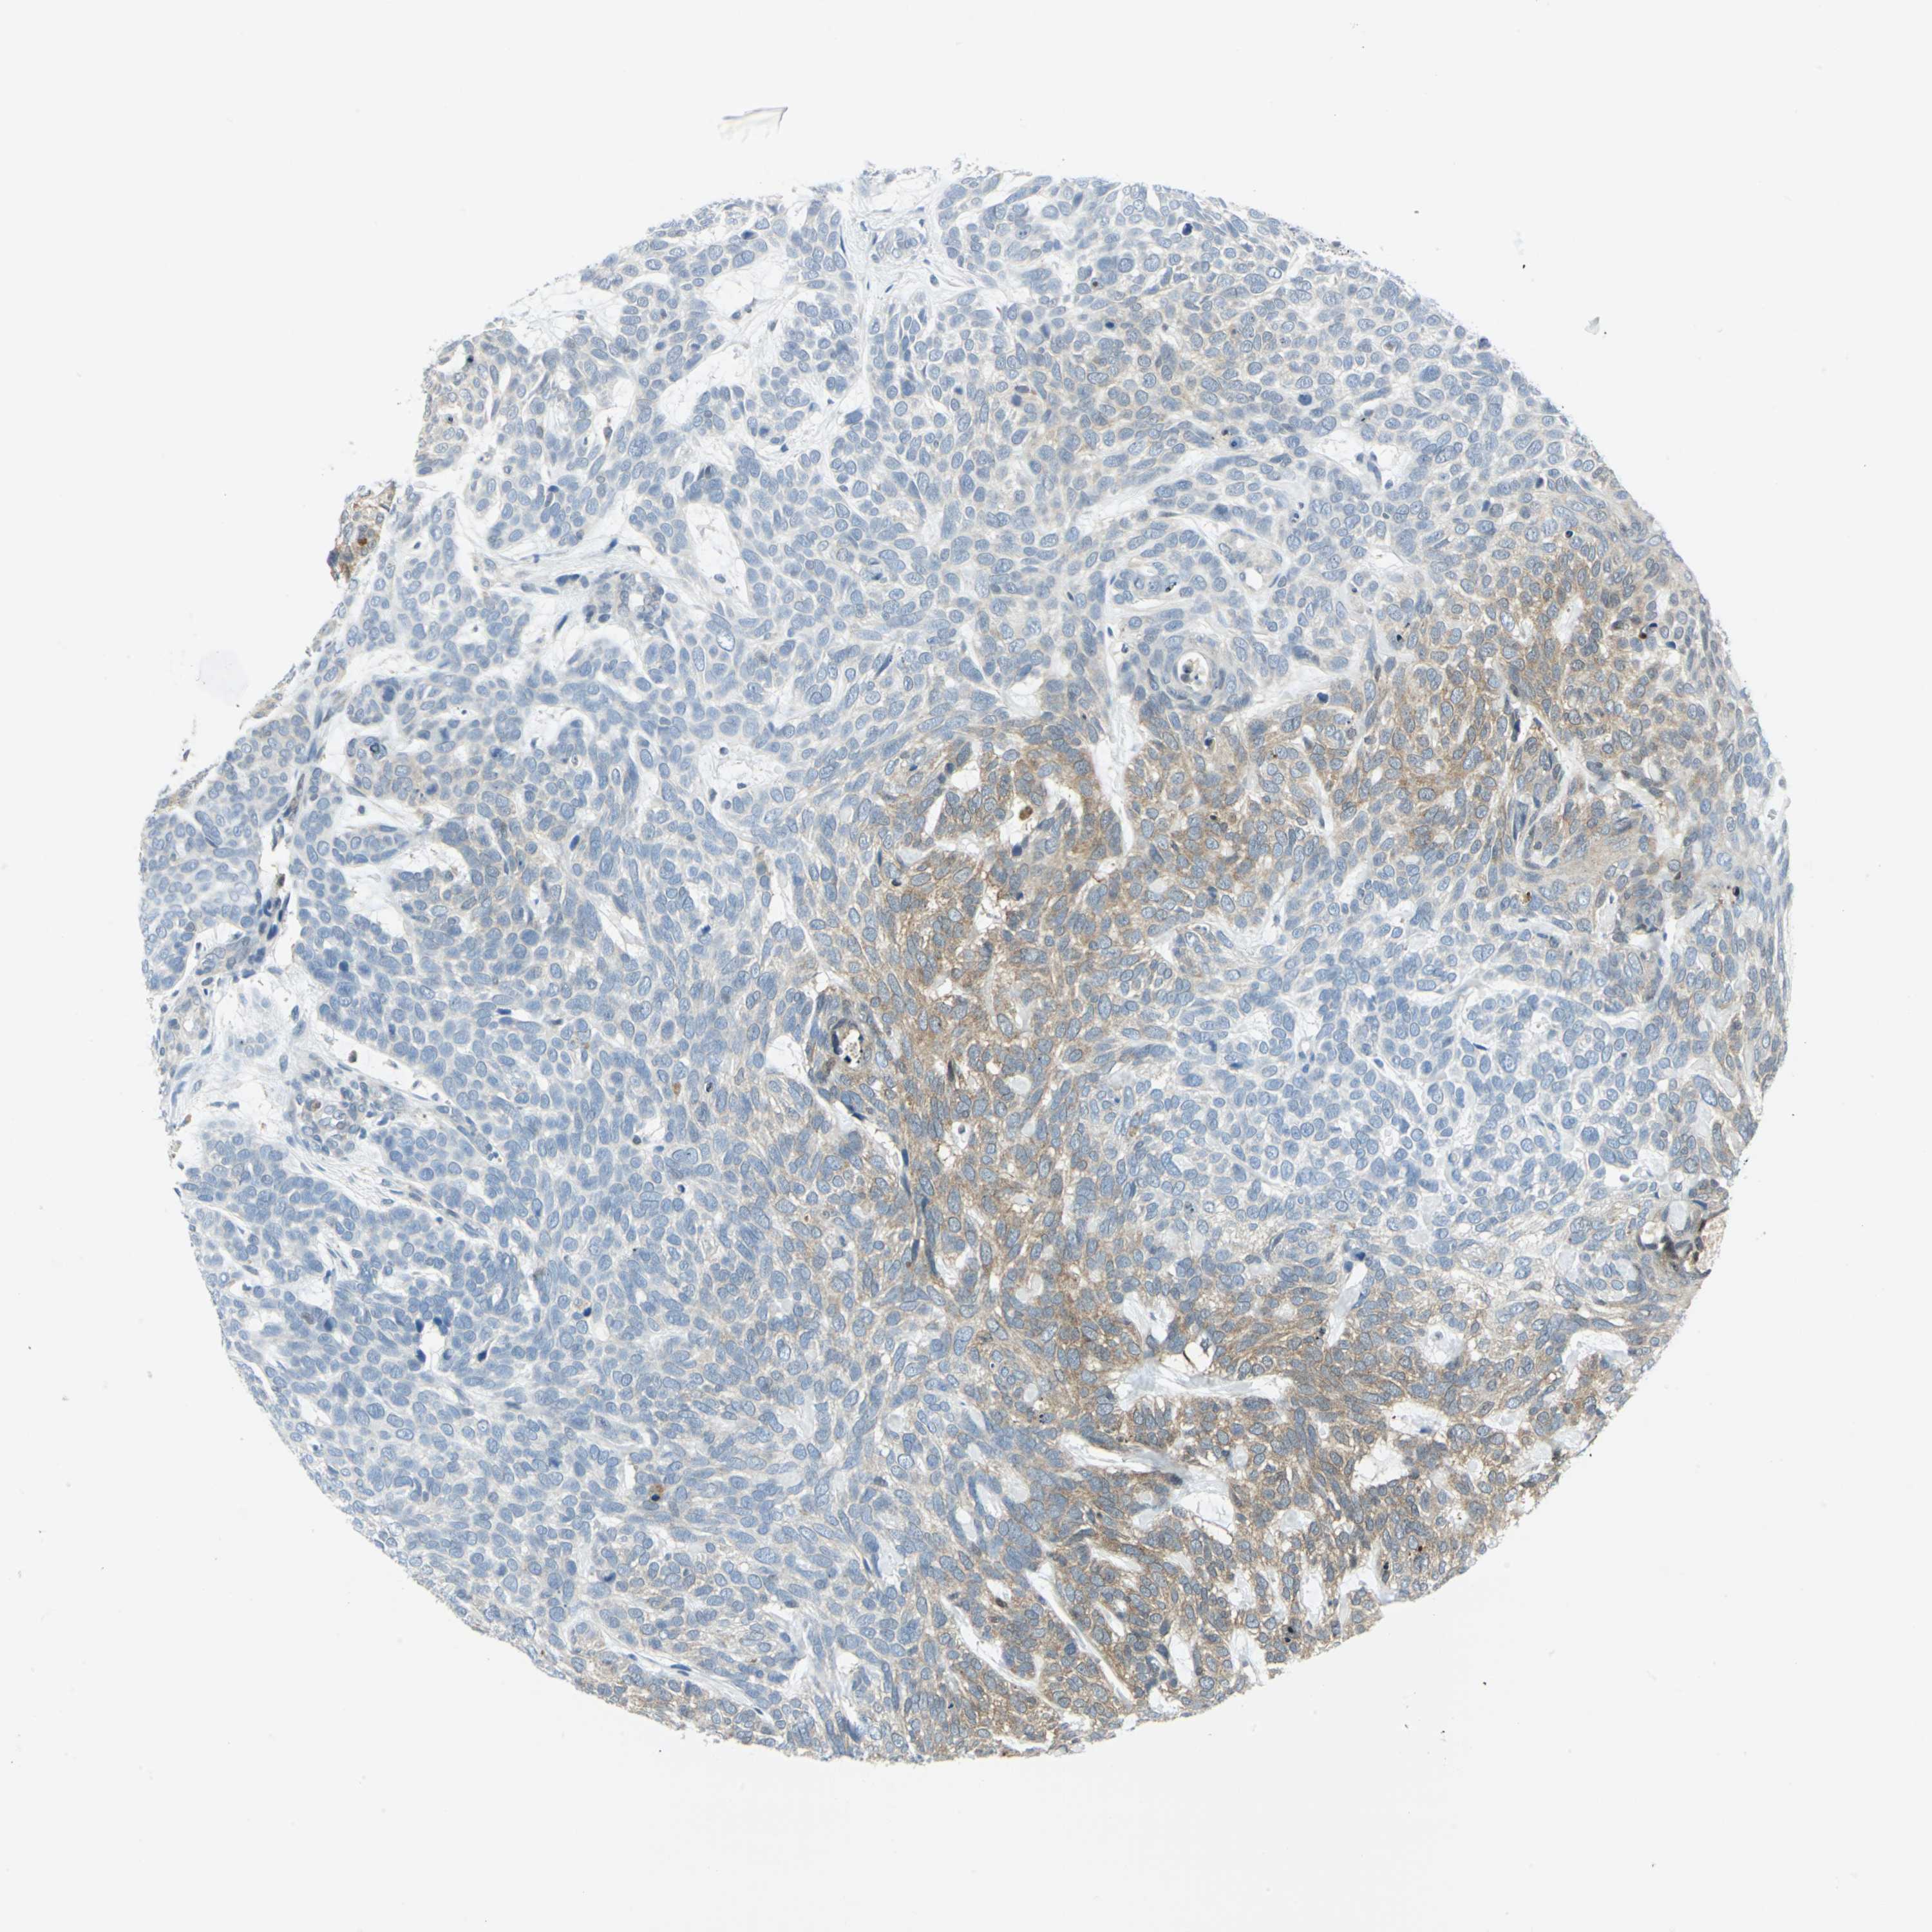

SKIN CANCER - Protein expressioni

A mouse-over function shows sample information and annotation data. Click on an image to view it in a full screen mode. Samples can be filtered based on level of antibody staining by selecting one or several of the following categories: high, medium, low and not detected. The assay and annotation is described here.

Each image is clickable and will lead to virtual microscopy that enables deeper exploration of all samples and also displays staining intensity scores, fraction scores and subcellular localization as well as patient and tissue information for each sample.

Antibody CAB006252

Staining

High

Medium

Low

Not detected

Intensity

Strong

Moderate

Weak

Negative

Quantity

>75%

75%-25%

<25%

None

Location

Nuclear

Cytoplasmic/membranous

Cytoplasmic/membranous,nuclear

Squamous cell carcinoma, NOS